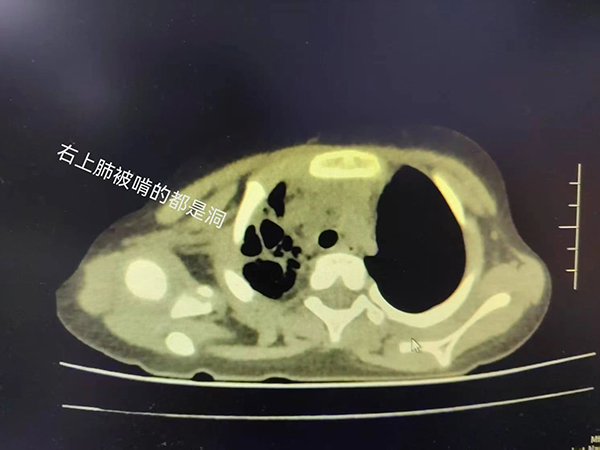

入院后的胸部CT证实了我们的判断,病情不容乐观!热程已拖到10天,秉承着重症感染抗炎要重拳出击的原则,我们马上予以强有力的联合抗炎治疗,力求最快控制感染,并迅速安排了支气管镜术,在短时间内取得了病原结果,竟是“肺炎链球菌”这个经典的家伙!它的威力可不容小觑,只不过几天,小朋友的肺子就被啃成了“筛子”!

早期可见肺纹理增强或局限于一个节段的浅薄阴影,之后可能会出现大片状阴影,占全肺叶或一个节段。少数患者出现肺大疱或胸腔积液。个别肺炎链球菌肺炎出现化脓性并发症,可出现肺实变区的坏死病灶(看起来像是肺子成了筛网),或出现支气管肺胸膜瘘或大小不等的脓肿等。